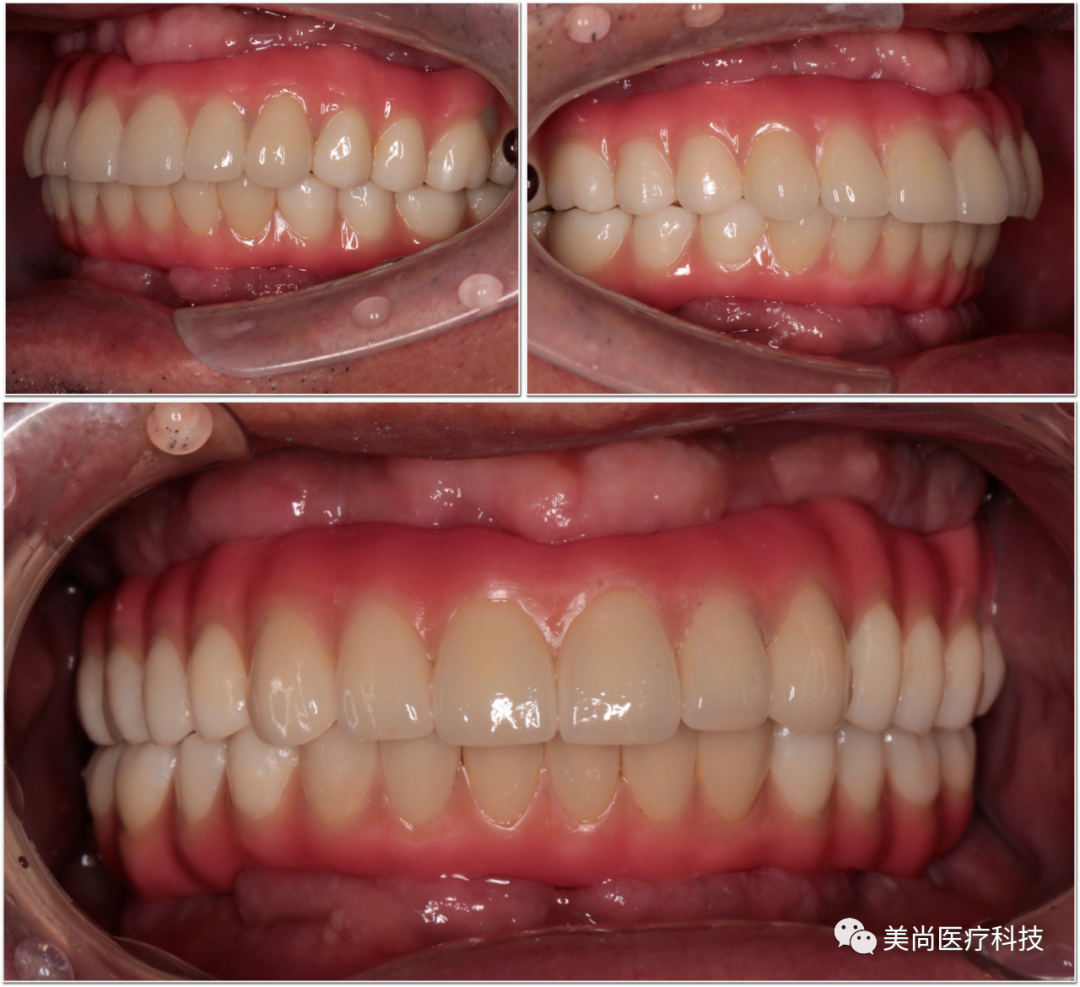

▲口内余留21,22,23,42,43,44,其余牙齿缺失,牙齿缺失区牙槽嵴明显萎缩

▲口腔卫生环境差,余牙II度~III度松动

▲咬合关系丧失,下颌习惯性前伸